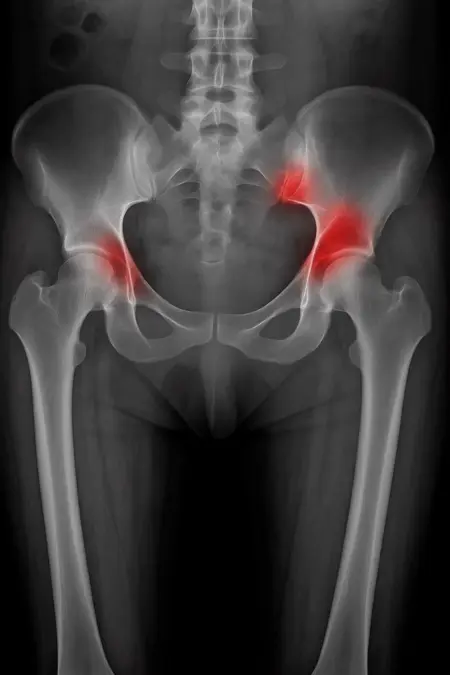

アートや写真の編集用に設計されたFlux Kontextのようなモデルを、医療画像、たとえば「単純な」骨折の赤色マーキングに使用できるか?

即答:面白い結果を出すが、過剰に反応し、医療ツールとしては信頼性に欠ける。これはアイデアを試すためのプロトタイプに過ぎない。

テスト結果:

- 偽陽性 ≈ 24%

- 骨折検出 ≈ 20%

感度モード(検出を優先、ノイズ多め)

- Euler、15ステップ、Karras

- Denoise:1.0

結果:

- 偽陽性 ≈ 80%

- 骨折検出 ≈ 86%

さらに攻撃的な設定(例:rk beta57、Denoise 1.0)では、**偽陽性100%、検出100%**という馬鹿げた結果に:すべてを赤で塗りつぶし、健常部もほぼすべて骨折と誤認する。未経験の目には区別がつかない。

Civitai用に作成した、100% AI生成の合成ミニデータセット(健康なX線10枚、骨折のあるX線10枚)でテスト:

- 健康な骨での偽陽性:100%

- 骨折検出:≈ 45%